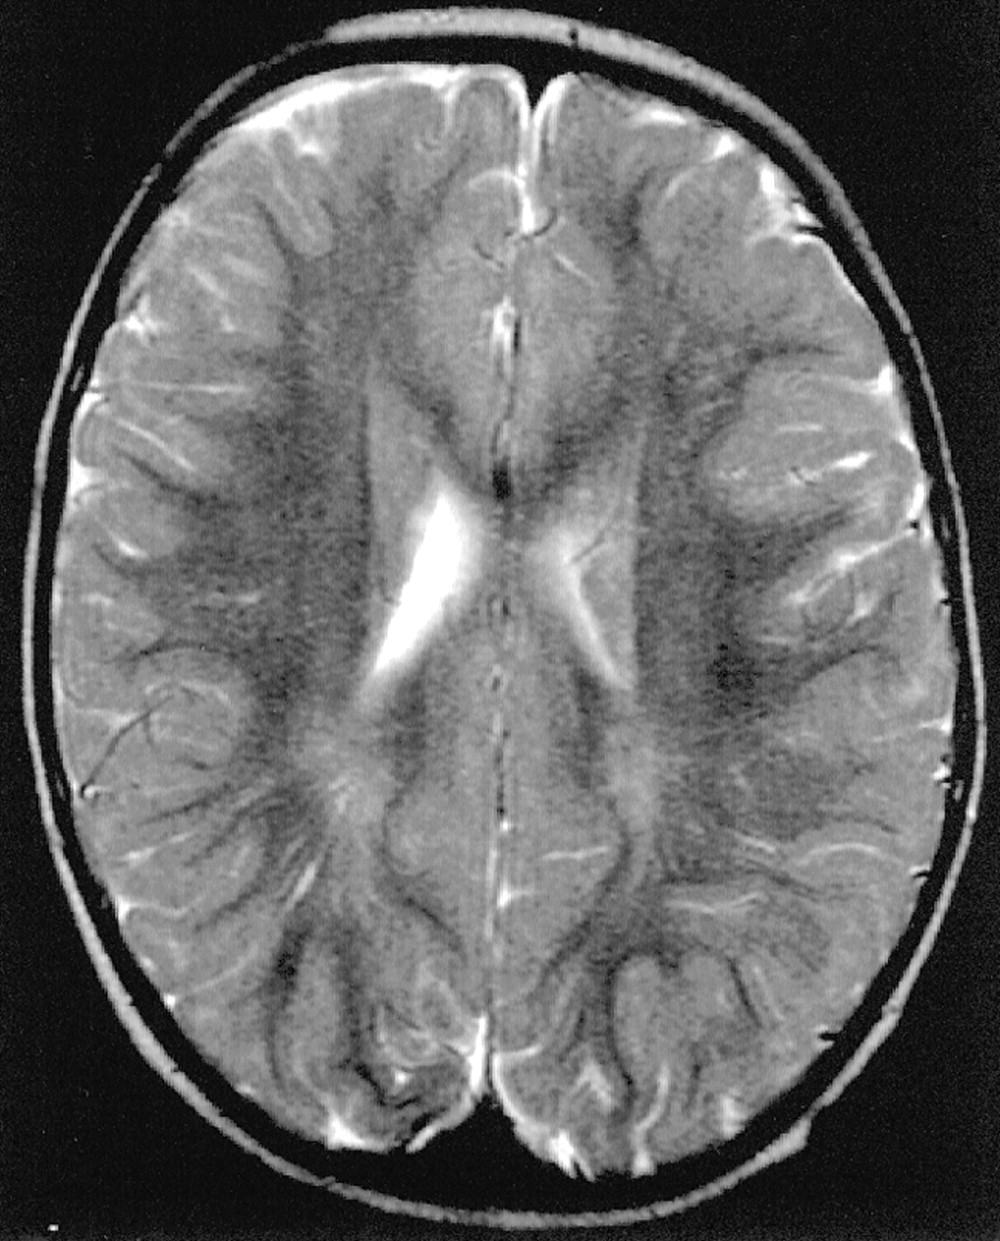

Our results confirm the topographical sequence of the development of myelination described in the anatomopathologic studies: the parietal lobe myelinates before the frontal and temporal lobes. In autopsy studies, the subcortical association fibers, connected with the highest intellectual functions, seem to complete their myelination in early adulthood (9–11). We noted that the subcortical regions are the last areas to myelinate. On radiologic studies, however, the terminal area of myelination is still considered to be the peritrigonal region. One possible explanation is that the T2 hyperintensity sometimes revealed in the peritrigonal zones, particularly on the high-spatial-resolution images with a matrix of 512, could be partially referred to perivascular spaces; images of linear T2 hyperintensity going from the ventricle walls toward the periphery were in some cases well visualized (Fig 7). The persistence of this aspect in people between the first and second decade of life would confirm this hypothesis even if further studies about the evolution of perivascular spaces in children and young people are necessary. Although we do not have follow-up studies in our patients, the large number of children examined and the good distribution among the different months of age led us to hypothesize that the process of myelination is not finished at 2 years of age. Myelination proceeds into the following months and only at 36–40 months of age does it appear to be complete. The so-called terminal zones seem to be the subcortical areas rather than the peritrigonal area. Finally, identification of subcortical areas as terminal myelination zones in children aged 2–3 years is a necessary step to ruling out white matter disease of developing brain.

Axial T2-weighted MR image shows peritrigonal linear areas of hyperintensity that can be referred to perivascular spaces.